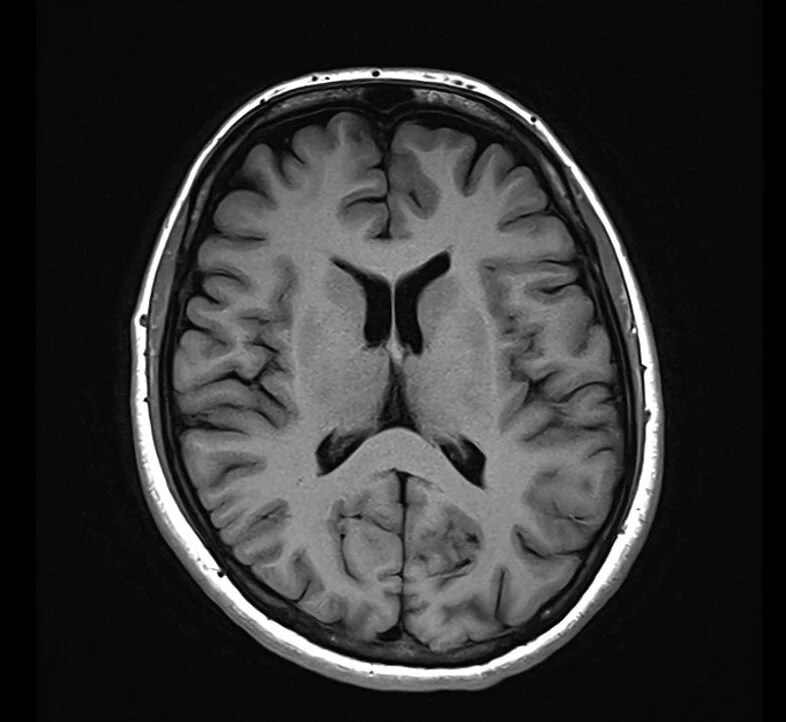

T1 Weighted Imaging

T1 is typically used as an informal anatomy scan.

Fat is Bright (quickly realigns its longitudinal magnetisation with B0)

Water is Dark (has much slower longitudinal magnetisation realignment after an RF pulse and therefore, has less transverse magnetisation)

Applications:

T1 focuses on highlighting anatomy

Useful to detect contrast

As contrast media goes to areas of high blood supply it can detect infections